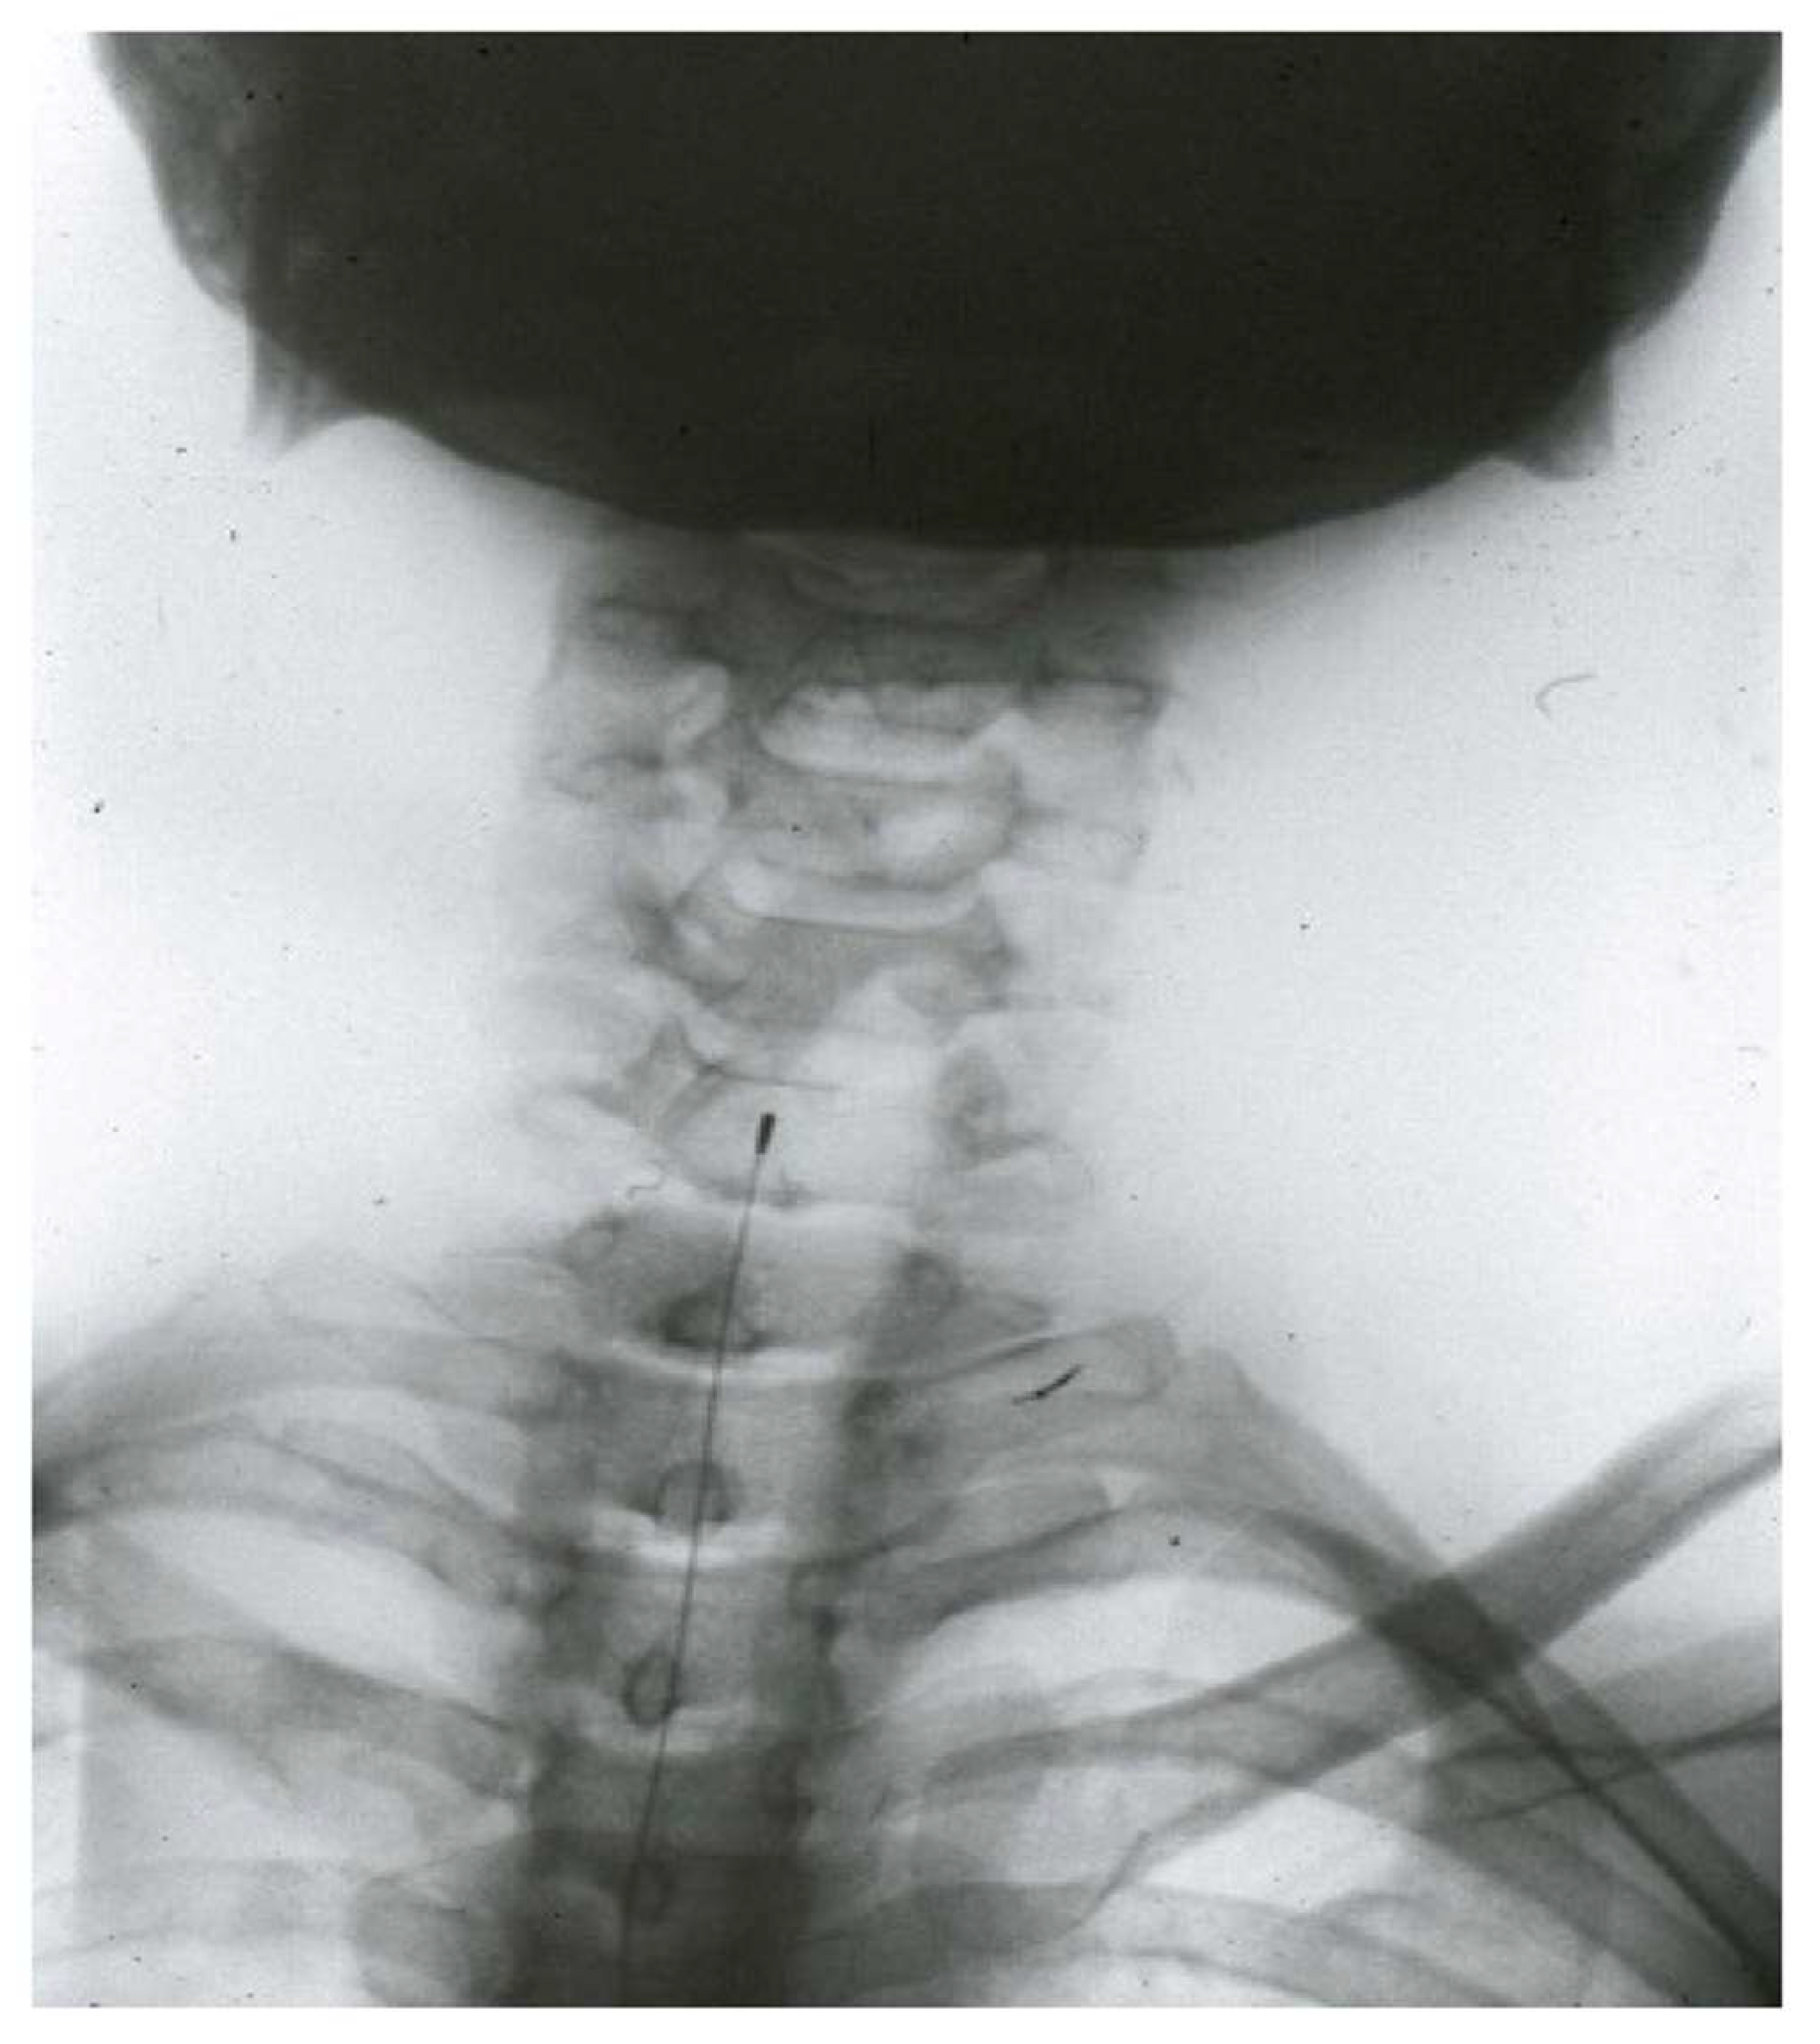

- Trigeminal tractotomy—The trigeminal tract also carries nociceptive afferents from cranial nerves VII, IX, and X. Sjöqvist [119] proposed in 1938 that this tract be severed, just before entering the caudate nucleus. The procedure involves a transverse section, about 8 mm below the obex (Figure 10). It generates ipsilateral hypoalgesia in the face, mouth, pinna, back of the tongue, and pharynx. Hitchcock [115,116], in 1970, described a percutaneous technique.